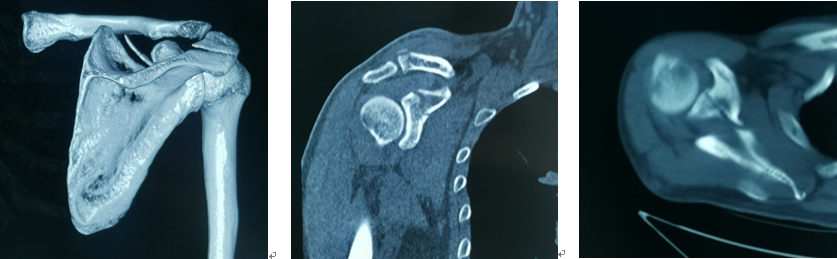

术前影像